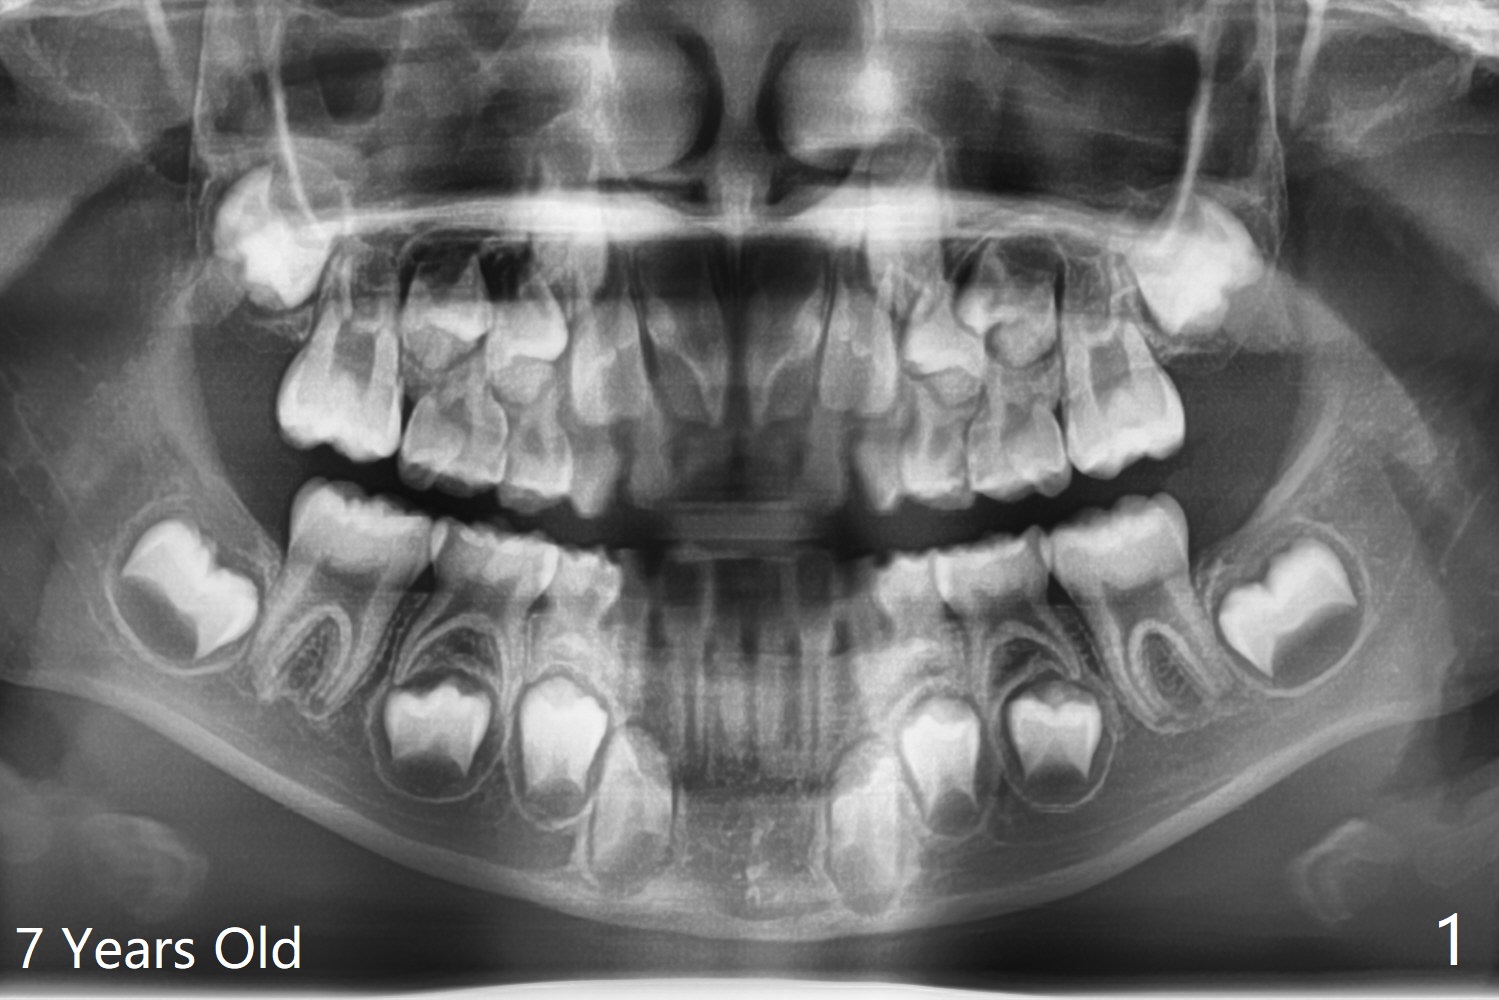

7岁女孩龋齿(图一)到八岁发展的严重(图二,三 (D))。为了有完整支抗,利用树脂(而不是不锈钢牙冠)保留左上第一乳磨牙(图六:D),以后可以安置矫正器。面部匀称(图七至十)。乳尖牙,第一恒磨牙:第一类咬合(图十一,十二)。左上前牙拥挤比右边轻,因为左上D龋齿破坏(图十三:D)。前牙扩弓时,右上D近中需要片切(^)。下颌拥挤轻(图十四),矫正器可以迟放置。